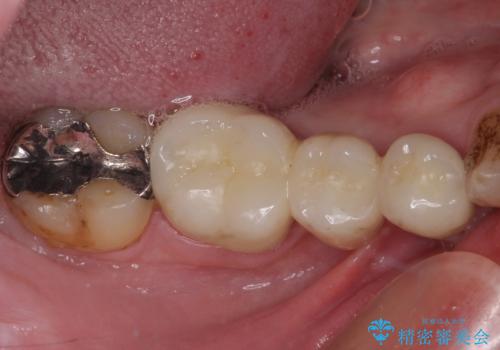

- 下顎前歯が抜けそうとのことで来院された患者様です。

初診の状態ではすぐにでも抜けそうな状態で、インプラントによる補綴治療を行うこととしました。

インプラント治療に際し、前歯の叢生に対する矯正治療を提案したところ、興味を持たれたので、インビザライン・ライトによる矯正治療を行うこととしました。

抜歯後にスペースができると恥ずかしいため、抜歯した歯を接着剤で固定した上で矯正治療を行い、その後インプラントやオールセラミッククラウンの装着を行うこととしました。